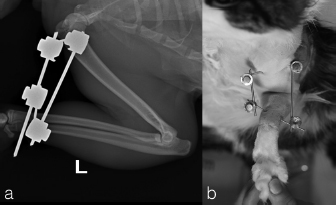

Two, spayed, Domestic Shorthaired cats with an age of 1.5 years (case 1) and 6 years (case 2) were referred to the author’s clinic for the non-weight bearing left forelimb lameness after a suspected trauma. Physical examination, of both cats, revealed moderately swollen and painful left elbow, with abnormal posture characterized by extended rotation of antebrachium and supination of the paw. Orthogonal radiographs of forelimbs demonstrated a complete caudal elbow luxation (Fig. 1). The radius and ulna were caudally and proximally displaced in relation to the humerus; furthermore, in case 1, a small avulsion bone fragment (2 mm diameter) closed to the lateral aspect of the humeral condyle was presented. No other abnormality was identified during the physical and radiographic examinations. The cats were sedated by intramuscular administration of dexmedetomidine (Dexdomitor: Pfizer Italia Srl, Rome, Italy) (10 μg/kg) and methadone (Semfortan: Dechra Veterinary Products Srl, Turin Italy) (0.4 mg/kg). General anesthesia was induced with propofol (Proposure: Merial Italia Spa, Milan, Italy) (6 mg/kg) intravenously and, after oro-tracheal intubation, maintained with isoflurane (IsoFlo: Aesica Queenborough Limited, Kent, United Kingdom) and oxygen. Modified closed reduction technique was attempted in both cases. Distal traction of antebrachium with full extension of the elbow was initially achieved followed by simultaneously applying distal pressure on the olecranon and partial elbow flexion. Following successful reduction, the collateral ligaments integrity was indirectly assessed with the Campbell’s test (1971), with normal limits value around 110° of supination and 70° of pronation recorded in both patients. The joint stability and reduction were maintained with gentle manipulation. However, instability was present at 100° of elbow extension, while major stability was obtained at 40° of flexion. For this reason, the elbow was held at 40° of flexion and a simple transarticular external skeletal fixator type IIa was applied to maintain the stability of the joint. Due to the forced flexion position, which limited the biomechanics movement, the cats were not able to weight bearing in the postoperative period. Two full pins, smooth Kirschner wires 2.0 mm of diameterf were inserted in the proximal third of the diaphysis of the humerus and in the distal third of the radial diaphysis. Stainless steel connecting bars (Gènia. St. Hilaire de Chaléons, France) (3.0 mm) were positioned medially and laterally connecting with Maynard clamps (Gènia. St. Hilaire de Chaléons, France) to the full pins (Fig. 2). The avulsion bone fragment was not treated in case 1. The patients were discharged from the clinic 24 hours after surgery. Cage rest without any exercise was recommended for 2 weeks and meloxicam (Meloxoral: Fatro S.p.A., Ozzano Emilia, Italy) (0.05 mg/kg) was administrated for 7 days.

Fig. 1. Pre-operatively radiographs in lateral (a, c) and cranio-caudal (b, d) view. Case 1 (a–b); case 2 (c–d).